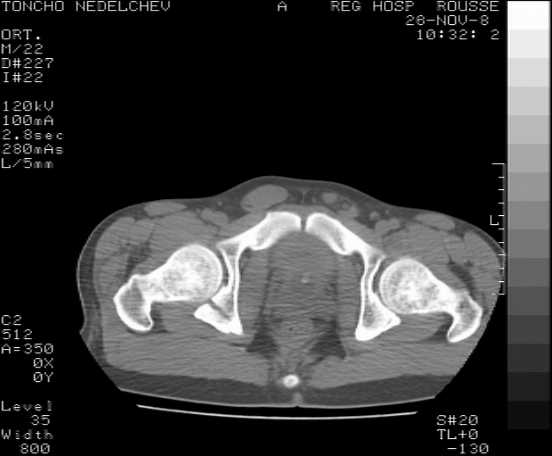

The details of the fracture are not so clear from the images sent...would you be able to send along an AP and Judet images as well as some additional axial images above and below the joint?

I’m not so sure that your patient has a Tr+PW pattern based on the images sent...maybe the fracture’s exact name won’t matter in the long run, but it’d be great to see enough images to make an accurate comment.

Without complete CT images and/or oblique radiographs, it's difficult to answer your question definitively, but it appears that there may not be a posterior wall fracture that requires a posterior approach. A successful reduction through an ilio-inguinal approach will have a faster recovery, and not risk SGN injury or heterotopic ossification.

Here are some more axial images. What is your opinion as for the timing of the operative treatment?